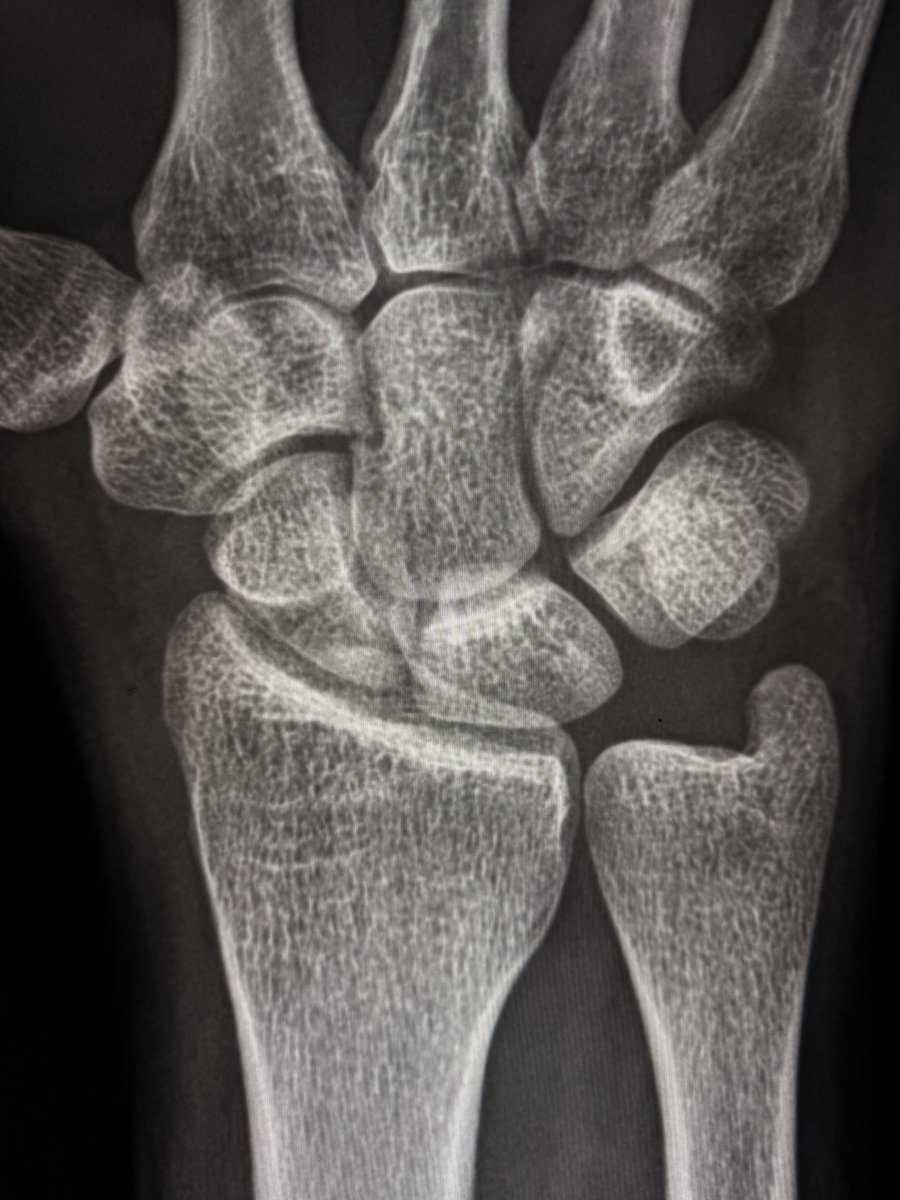

A large dorsal talar beak on sagittal CT or lateral ankle radiograph.

Talar beak is a marker of restricted subtalar motion, not a diagnosis. In a young patient, actively search for a subtalar coalition.

This case showed a fibrous coalition of Medial accessory talocalcaneal articulation at the level of the posterior sustentaculum tali, between the Talus and Calcaneus.

Wisdom: A talar beak should trigger a search, not end it.